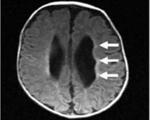

• Нейровизуализация. При КТ и МРТ головного мозга определяются множественные очаги атрофии белого вещества, часто визуализируются кисты перивентрикулярной области размером более 4 что коррелирует с тяжелым неврологическим дефицитом.